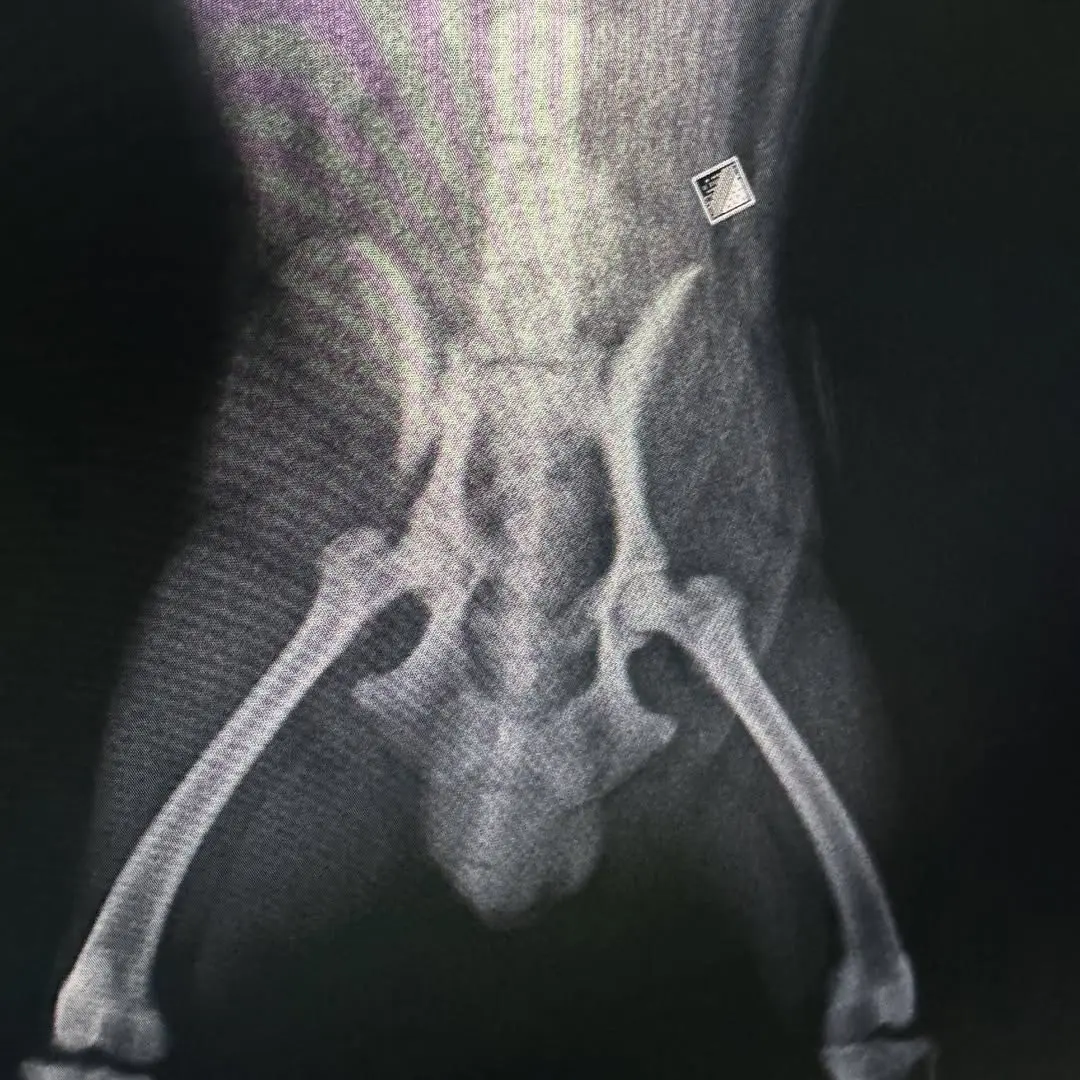

Pelvis ve Kalça Kırıkları: Parçalı pelvis kırıkları ve kalça çıkıkları, özel tekniklerle tedavi edilir.

Görüntüleme ve Tanı: Röntgen, ultrason gibi görüntüleme yöntemleriyle tanı konulur.